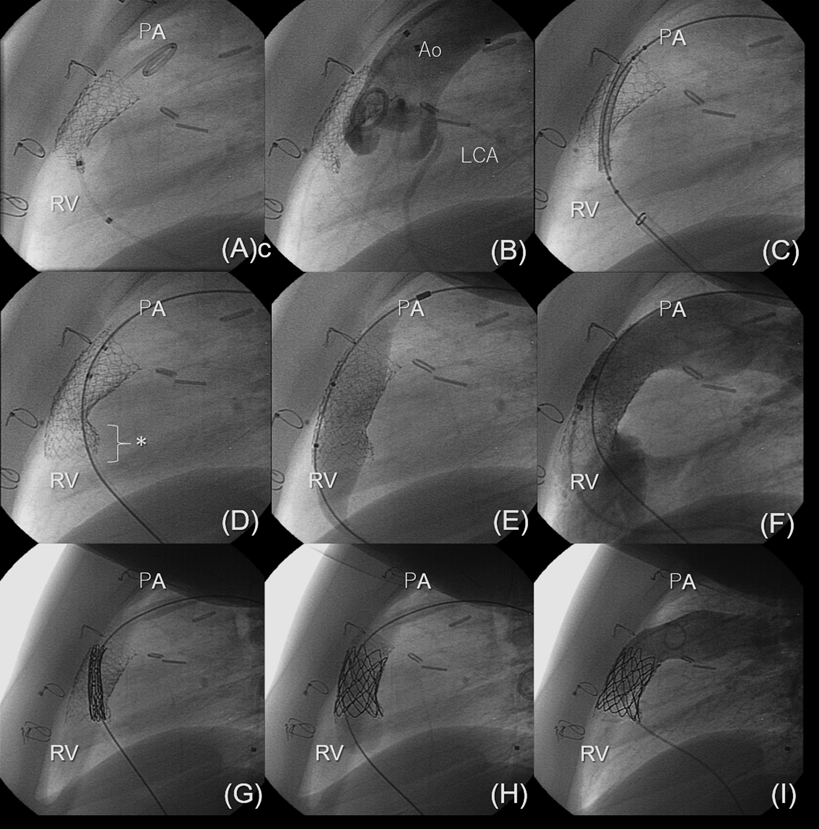

Pediatric Cardiology and Cardiac Surgery 36(1): 23-35 (2020)

Fig. 3 Angiogram during transcatheter pulmonary valve replacement

Angiogram (left anterior oblique projection) demonstrates the recoil of the stent implanted three months ago in 16-mm homograft which showed significant stenosis (A). Angiogram shows distance between main pulmonary artery and left main coronary artery (*) (B). Additional stent as implanted to open the recoil (C, D). Additional inflation was performed to gain the inner diameter (E). Acceptable opening of the homograft was achieved (F). Melody valve was positioned and implanted in the double stent (G, H). The final angiogram demonstrates good valvular competence and good acceptable opening of the homograft (I). Ao: aorta, PA: pulmonary artery, RV: right ventricle